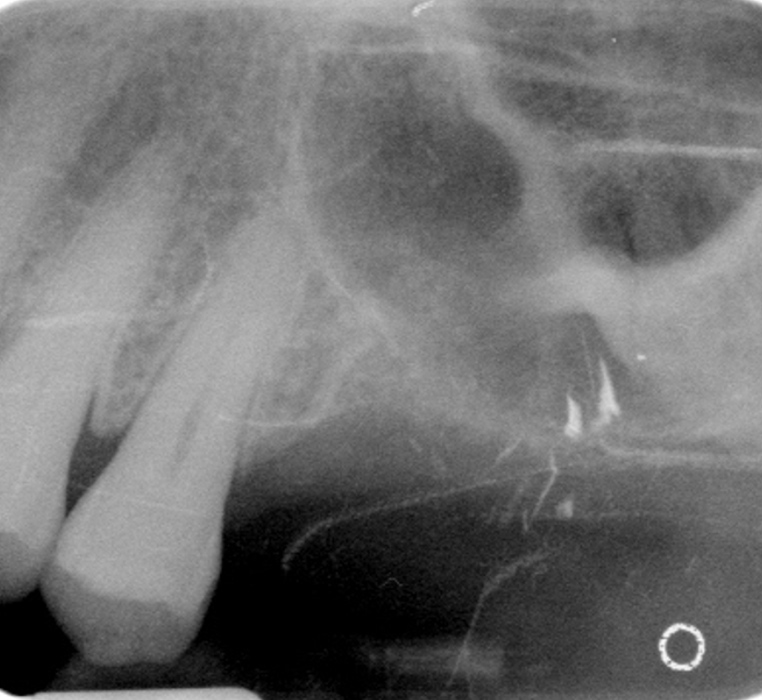

Left Maxillary Sinus Graft for Dental Implant

Before